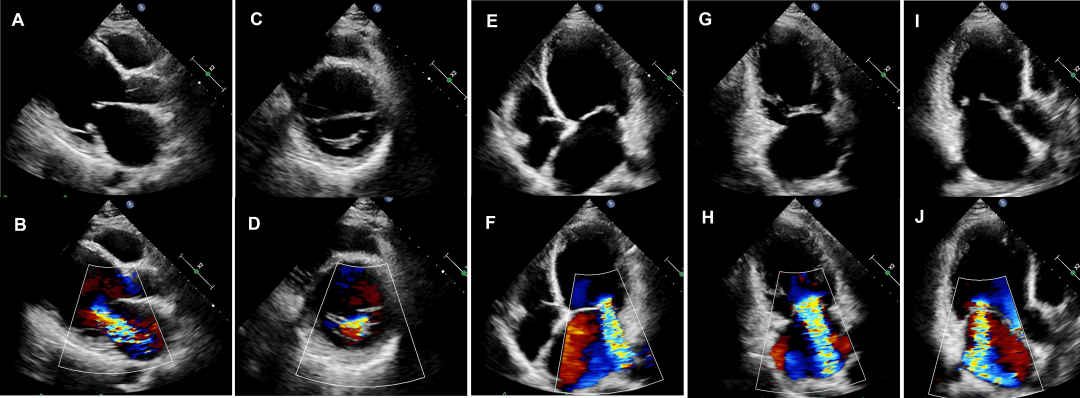

二尖瓣装置包括瓣环、瓣叶、瓣下腱索、乳头肌及其附着部位的左心室壁。超声心动图可通过多切面对二尖瓣的解剖结构和功能进行评估。经胸超声心动图(TTE)的观察切面主要包括胸骨旁左心室长轴切面、胸骨旁二尖瓣水平及乳头肌水平短轴切面、心尖四腔心、两腔心及心尖长轴切面等(图1)。

图1 经胸超声心动图常用于观察二尖瓣的切面

A、B 胸骨旁长轴切面及彩色血流图;C、D 胸骨旁二尖瓣水平短轴切面及彩色血流图;E、F 心尖四腔心切面及彩色血流图;G、H 心尖两腔心切面及彩色血流图;I、J 心尖长轴切面及彩色血流图